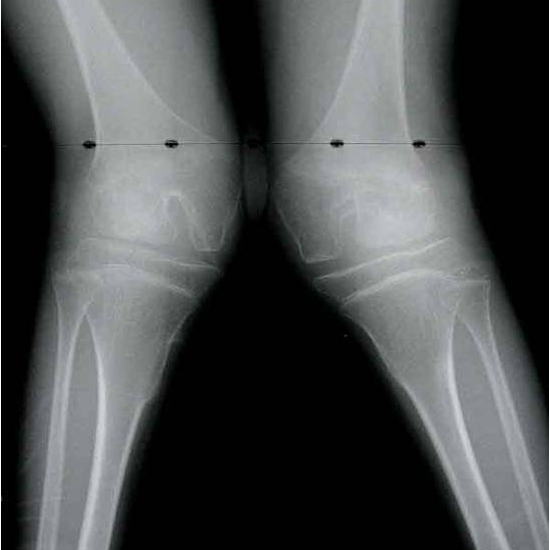

X-rays of the neck, thoracic, and lumbar spines, as well as the lower extremities